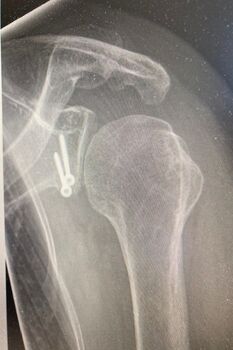

Bild Patient Schulterluxation nach der OP

69-jähriger Patient mit linkseitiger Schulterluxationsverletzung. Bei älteren Patienten kommt es im Rahmen der Schulterverrenkungen häufiger zu Sehnenabrissen am Oberarmkopf. Trotz der Einrichtung des Gelenkes kann der Arm nicht wieder gut bewegt werden. Erst die operative, in diesem Falle rein arthroskopische Rekonstruktion der Sehnen und deren Einheilen ist eine Schultergelenksbewegung wieder gut möglich.